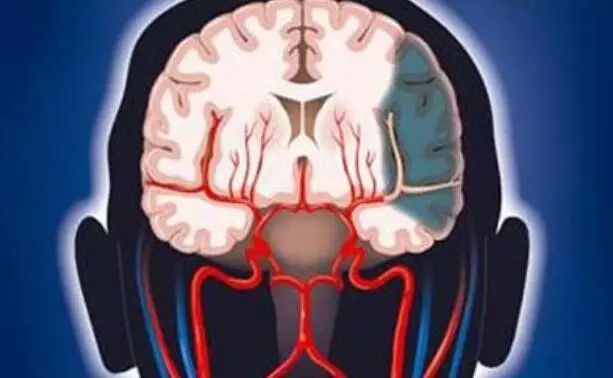

常为双侧硬脑膜下血肿,尤其是小儿及老年病人,因额部或枕部减速性损伤所致。当致伤暴力大、脑挫裂伤严重时,常为急性硬脑膜下血肿,往往位于双侧额颞前份。

若脑原发性损伤轻微,系脑表面的桥静脉撕裂出血时,则多为慢性或亚急性双侧半球凸面硬膜下血肿。偶尔可因挤压伤致双侧颞骨骨折,亦有引起双侧硬脑膜外血肿的可能,但较少见。